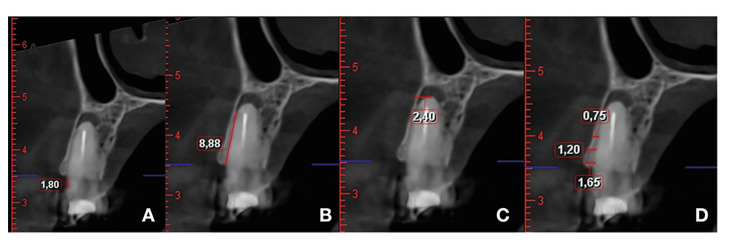

Material and methods: A prospective study was conducted involving patients with persistent periapical disease undergoing periapical surgery, with one year of follow-up. Data collected included patient age, gender, teeth involved, and the number of roots/lesions. CBCT measurements were taken preoperatively and one year post-surgery, including the distance from the cementoenamel junction to the buccal bone crest (CEJ-BBC), marginal bone loss, buccal cortical height, presence of fenestration, apical depth, cortical bone width at 1, 3, and 5 mm from the buccal bone crest, and lesion volume in mm³. Success was assessed using the "Modified Penn 3D criteria."